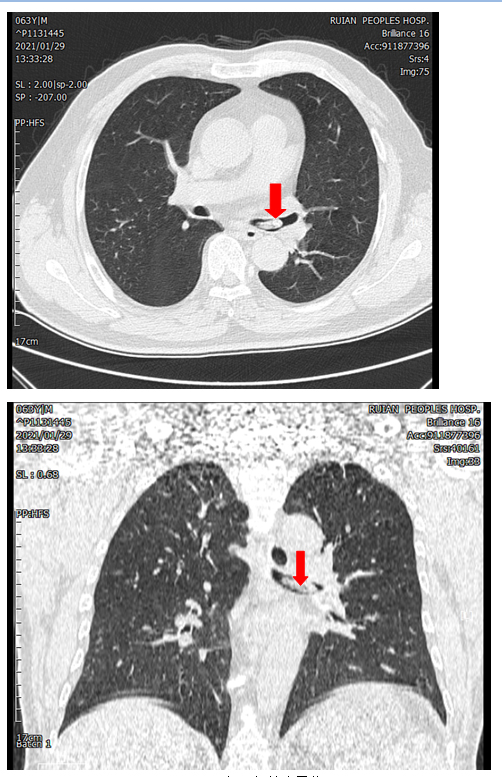

日前,一位张大叔在与朋友吃饭时边聊天边吃饭,一个不小心,一只虾顺着他的喉咙,呛进了气管。张大叔瞬间咳得满脸通红,拍着自己的前胸想要努力咳出来,但是徒劳无功,虾没咳出来,一阵一阵的剧烈咳嗽和胸部憋闷感让他非常的不舒服,于是在家人的陪伴下来到了我院呼吸与危重症医学科门诊就诊,接诊的医生询问了病史后给张大叔查了胸部CT。

CT提示气管内异物

左主支气管内可见白虾的头部,长长的虾须延升至隆突处